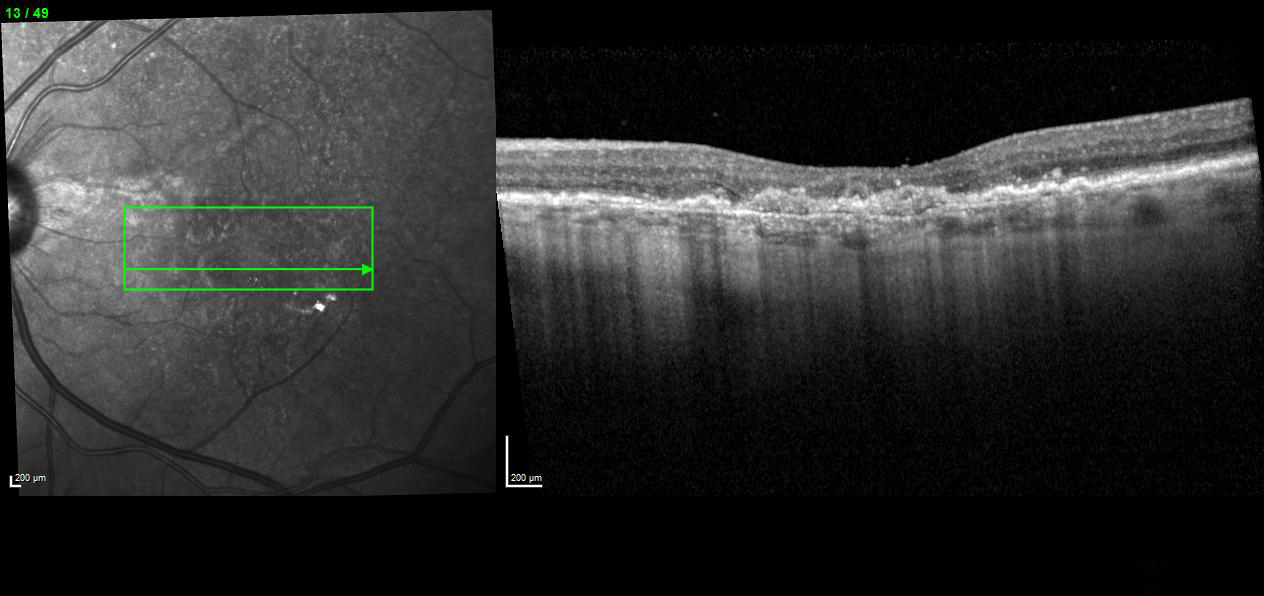

Actual Review: (Referral sent to Dr. Lee Feb 4, 2025) Agree with your assessment. This patient has wet age-related macular degeneration in the left eye.

Fundus photos show drusen and geographic atrophy. OCT and OCT angiography confirms  choroidal neovascularization. The patient needs treatment with anti-VEGF.